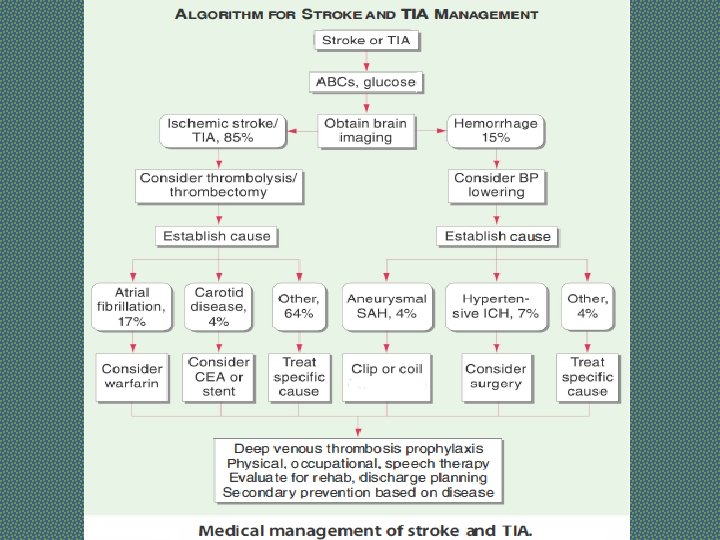

Stroke Ischaemic stroke/infarction (80%) Ø Thrombotic Ø Cardio-embolic Ø Large artery stenosis Ø Small vessel disease Ø Hypoperfusion Haemorrhagic stroke (17%) Ø Intracerebral hemorrhage (12%) Ø Subarachnoid hemorrhage (5%) Other (3%), e. g. arterial dissection, venous sinus thrombosis, vasculitis

Types of Stroke Depending upon the rate of developing and reversibility, stroke can be of following types: § Transient Ischemic Attack (TIA): means a brief episode of neurological dysfunction due to temporary focal cerebral or retinal ischemia without infarction, e. g. a weak limb, aphasia or loss of vision, usually lasting seconds or minutes with complete recovery. § Stroke-in-Evolution: If neurological deficit increases by step wise progression or there is slow uninterrupted progression, it is called stroke-in-evolution. It may take 12 weeks to complete § Complete Stroke: It means complete hemiplegia § RIND (Reversible Ischemic Neurological Deficit): It is a term that is not widely used anymore. It means a stroke that the patient was able to fully recover from within a few weeks.

ISCHEMIC STROKE Cerebral Thrombosis: § § § Occurs when patient is asleep Atherosclerotic narrowing of blood vessel Middle cerebral art is commonly involved Patient usually remain conscious HTN is a major risk factor Clinical Features: ØPt can not move one half of body ØDysphasia ØUncrossed hemiplegia ØHigh BP ØCarotid Bruit

ISCHEMIC STROKE Cerebral Embolism: § Sudden onset § Past history of TIAs § Source of Embolism q Carotid artery atheroma (weak carotid pulse, bruit) q Atrial Fibrillation or other arrythmias q Recent Myocardial Infarction q Valvular Heart Disease q Infective Endocarditis § Clinical Features: Ø Sudden loss of power in one half of body Ø Conciouness may be lost Ø Dysphasia Ø Uncrossed hemiplegia Ø Irregular Pulse Ø Signs of valvular heart disease Ø Carotid Bruit

HEMORRHAGIC STROKE Primary Intracerebral Hemorrhage: § H/O HTN § Internal capsule is most common site. Other sites: subcortical white matter, pons, and cerebellum. § Occurs when pt is engaged in some activity § Causes: HTN, Saccular Aneurysm, AV Malformation, Bleeding Disorders § Clinical Features: ØSudden loss of power in one half of body ØHeadache, vomiting and loss of Conciouness ØUncrossed hemiplegia ØFundoscopy: Papilledema

HEMORRHAGIC STROKE Subarachnoid Hemorrhage: § Primary: Bleeding occurs directly into subarachnoid space. § Causes: Saccular Aneurysm, AV Malformation, Bleeding Disorders, Vasculitis § Clinical Features: ØSudden onset of severe Headache with or without vomiting ØSOMI are present ØFocal neurological signs ØFundoscopy: Subhyloid hemorrhage, Papilledema Secondary: Extension of intracerebral hemorrhage into subarachnoid space

MIDDLE CEREBRAL ARTERY • Supplies lateral surface of frontal, perital and temporal lobes • Most of the motor and sensory cortex Ecxept the part on medial side and control lower limb, internal capsule Total Occlusion: • Uncrossed hemiplegia • Hemianesthesia • Global Dysphasia • Homonymous hemianopia • Apraxia, Agnosia Partial occlusion: • Any of the above features. • Lower limb is either not or minimally involved

ANTERIOR CEREBRAL ARTERY • Supplies MEDIAL surface of hemisphere • Motor and sensory cortex on medial side which control lower limb • Soon its origin it gives a penetrating branch (Heubner’s artery) which supply internal capsule (containing fibers of upper limb and face) Occlusion at the origin: Features are similar to total occlusion of MCB Occlusion of Heubner’s artery : • Weakness of upper limb and face Occlusion after the origin of Heubner’s artery : • Weakness of lower limb • Loss of cortical sensory function in lower limb

POSTERIOR CEREBRAL ARTERY • Branch of Basilar artery • Supplies occipital lobe which include visual cortex Occlusion: • • Visual field loss Homonymous hemianopia Visual agnosia Disorders of reading Disorders of color vision Memory impairment Motor dysfunction